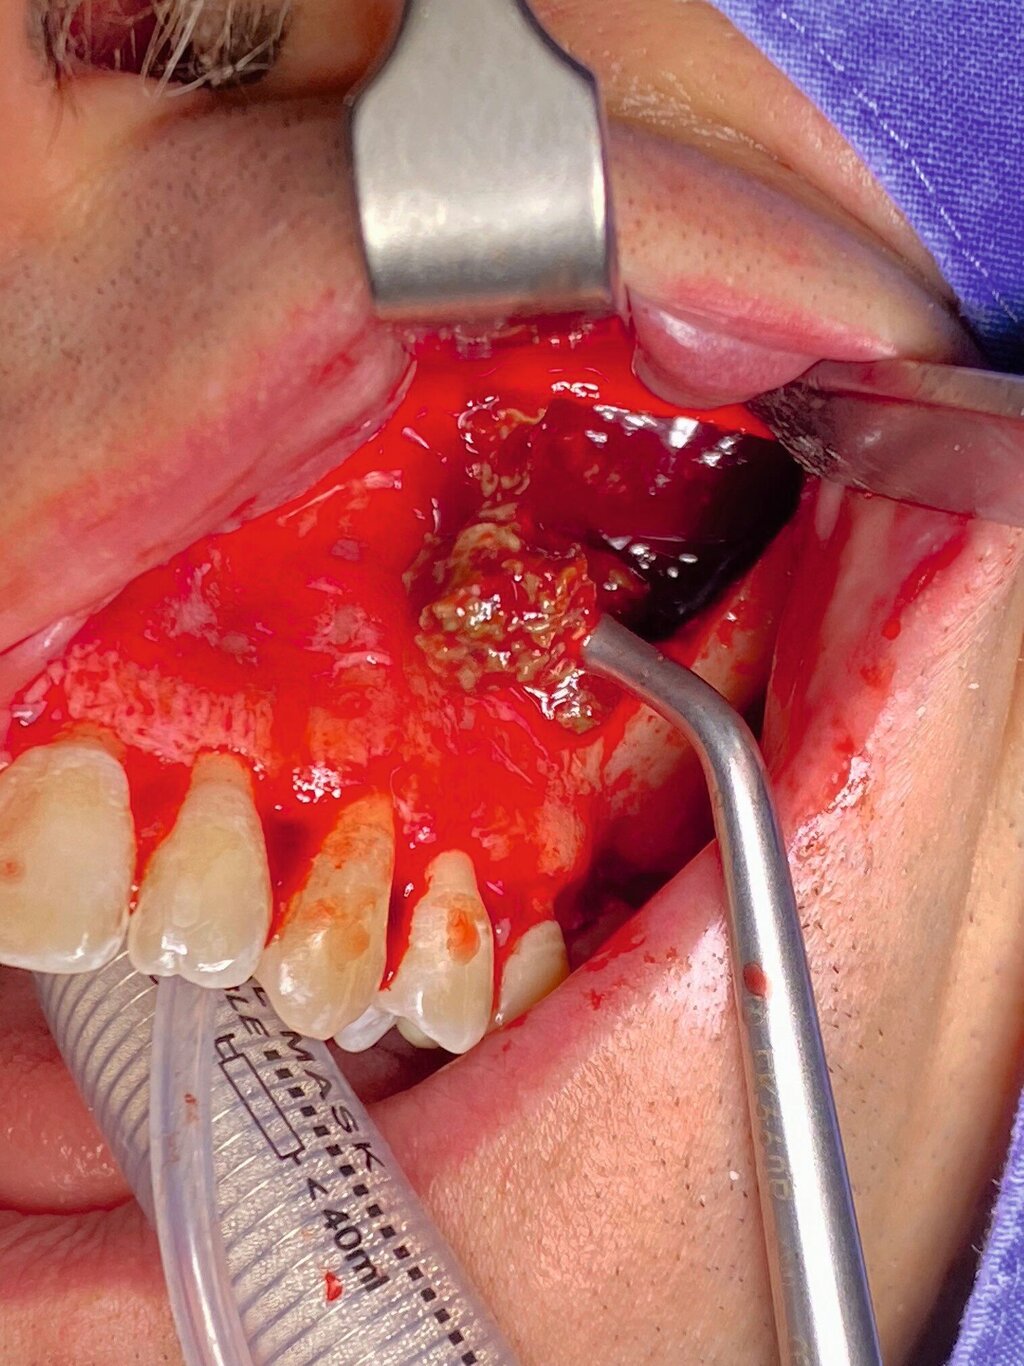

Die Therapie erfolgte in ambulanter Vollnarkose mittels Lindorf-Deckel-Technik. Nach marginaler Schnittführung und Darstellung der Kieferhöhlenvorderwand wurde mittels Piezosurgery ein knöcherner Deckel präpariert und der Sinus eröffnet (Abbildung 3). Es zeigten sich eine große Menge bröckeliges, schwarz verfärbtes Material sowie eine entzündlich veränderte Schleimhaut (Abbildung 4).

Zudem wurde ein Zahnkronenfragment geborgen (Abbildung 7). Die Kieferhöhle wurde unter Erhalt der auskleidenden Schleimhaut vollständig gereinigt und mit physiologischer Kochsalzlösung gespült. Zur postoperativen Spültherapie wurde transnasal ein Drainageröhrchen durch das Ostium naturale eingelegt (Abbildung 5). Auf ein Fenster zum unteren Nasengang wurde daher verzichtet. Der Knochendeckel wurde reponiert und mit resorbierbaren Nähten fixiert (Abbildung 6).

Die intraoperative Bergung braun-grauer bis grau-gelber und bröckeliger Weichgewebsmasse ist typisch für ein Aspergillom [Ciapuccini et al., 2017]. Der mikrobiologische Nachweis kann mittels Anzucht aus dem intraoperativ gewonnenen Material erfolgen, jedoch ist ein Zwischenergebnis der Kultur erst nach frühestens 24 bis 48 Stunden zu erwarten [McGinnis et al., 1977]. In der histologischen Aufarbeitung zeigen sich charakteristisch verzweigte Hyphen [Khongkhunthian et Reichart, 2001]. Im vorliegenden Fall wurde mit dem für die histopathologische Aufarbeitung gewonnenen Material eine zusätzliche PCR-Diagnostik durchgeführt, die auf den Nachweis von A. fumigatus schließen ließ.